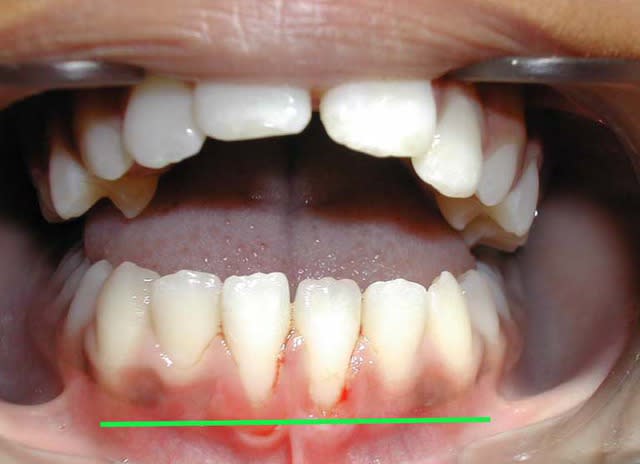

voici l'état de la gencive en fin de TTT. ORTHO

3 kemn9r - Eugenol

La question que je me pose est :

dois-je épaissir cette gencive très fine, (donc fragile), en face de 31/41 ?

@+ Bjc.